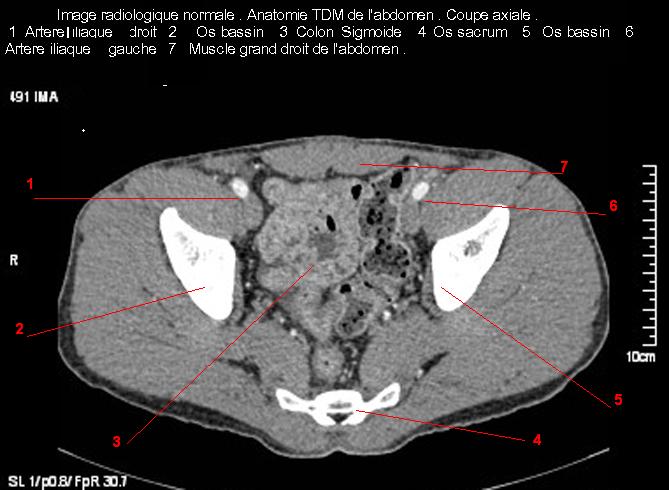

Image radiologique TDM normale de l' abdomen et tube digestif en coupe axiale ( CT scanner )  :

Coupe axiale     Coupe frontale      Coupe  sagitale